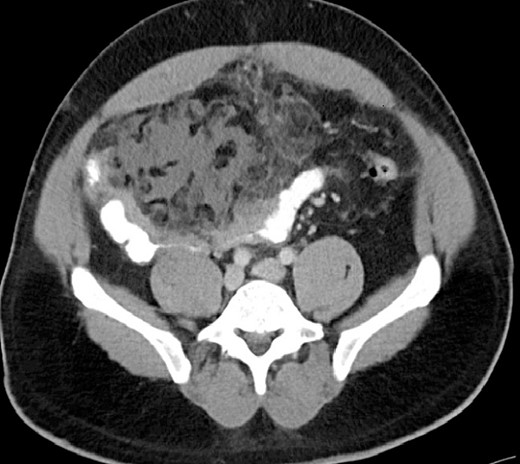

A 44-year-old male underwent an ambulatory, uneventful robotic-assisted laparoscopic left inguinal hernia repair and was discharged to home on the same day. On postoperative Day 16, he came back to emergency room with complaints of 3 days of right lower abdominal pain associated with fever and chills but no other gastrointestinal or urinary symptoms. Other than a temperature of 101.3 F, he was hemodynamically stable. BMI: 33.5 kg/m2. On physical examination, the abdomen was distended, with significant right lower quadrant tenderness, rebound, and localized guarding. The blood work was unremarkable. CT scan revealed localized focal omental edema and inflammation overlying small bowel wall edema and a small amount of free fluid in the lower abdomen (Fig. 1). The patient initially received intravenous hydration and a broad-spectrum antibiotic but failed to improve. He underwent a diagnostic laparoscopy which was converted to laparotomy due to extensive adhesions. Intraoperative findings included a small amount of serosanguineous free fluid in the right paracolic gutter, matted small bowel loops covered with fibrinous tissue, and wrapped within a portion of necrotic omentum. Resection of the omentum and dusky bowel (about 15 cm) with primary anastomosis were done. The patient was discharged in 5 days with no issue. The histopathology review of the omental tissue revealed extensive fat necrosis, focal ossification, and areas of abscess formation, along with focal organizing thrombosis. The resected small bowel had evidence of acute and chronic inflammation with micro-abscess formation involving muscularis propria and serosal surface and surrounding adipose tissue with extensive fibrinous adhesions. No evidence of thermal injury and no micro/macro perforation were seen. The culture of intra-abdominal fluid came back as bacteroides thetaiotaomicron and bacteroides vulgatus anaerobic gram-negative rods.

CT finding of OI with focal omental edema and inflammation overlying small bowel wall edema.